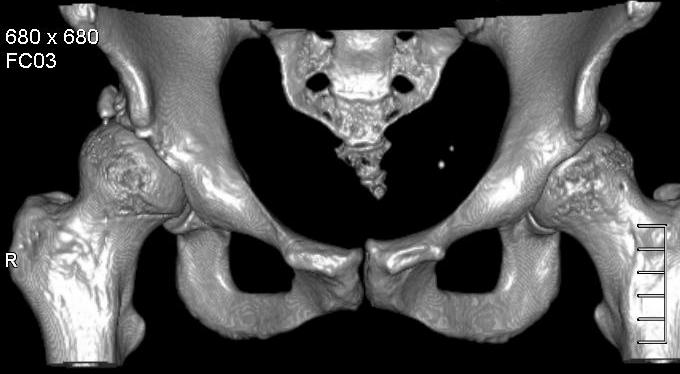

Добавляю снимков для "информационной поддержки принятия решения" (ну, нравится мне это выражение )). Поступило предложение выполнить артроскопию для оценки сохранности хряща. Насколько это необходимо?